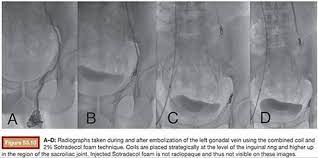

A retrospective study was conducted in 244. Sotradecol is not a cure for varicose veins and the effects of this medication may not be permanent. Post embolization portal venogram demonstrates complete embolization of the right anterior and posterior portal venous vasculature without contrast filling. It is visible via ultrasound and can be easily tracked and guided to the source of the problematic vein. This can be used for all vessel 2ml of.25% was used for the procedure. Sotradecol (sodium tetradecyl sulfate injection) is a sterile nonpyrogenic solution for intravenous use as a sclerosing agent. Polidocanol (asclera®) or sodium tetradecyl sulfate, known as sts (sotradecol®) is used. Abstract background treatment of congenital venous malformations poses a major clinical challenge. Sotradecol (sodium tetradecyl sulfate) injection is a sclerosing agent used to treat small, uncomplicated varicose veins in the legs. Each ml contains sodium tetradecyl sulfate 10 mg, benzyl alcohol 0.02 ml and dibasic sodium phosphate, anhydrous 4.0 mg in water for injection. The most frequently used agents are sotradecol (sts), foam, and coils. Has been administered as an endovenous foam or microfoam;

Small volumes (20cc max) of sotradecol sclerosant admixed with air are injected under fluoroscopy to ablate the epithelial cyst lining. 1% 20 mg/2 ml (10 mg/ml): Many agents have been used to occlude the isv. Has been administered as an endovenous foam or microfoam; 2ml of.25% was used for the procedure. Sotradecol foam was injected into each site under fluoroscopic guidance using negative contrast/contrast displacement technique (fig. It is visible via ultrasound and can be easily tracked and guided to the source of the problematic vein. However, when talking about doing sclerotherapy involving the legs, sotradecol is the more commonly accepted drug of choice. Is the best of the foam sclerosants. It is easy to use, has few side effects and gives excellent results. Asclera and sotradecol are both fda approved sclerosants and both have a very safe record for many years (even prior to fda approval in the generic form). There are a multitude of sclerosants out there, not all of which are appropriate for the legs. It is sold for medical use as a solution of up to 3% concentration with 2% benzoyl alcohol used as a stabilant.